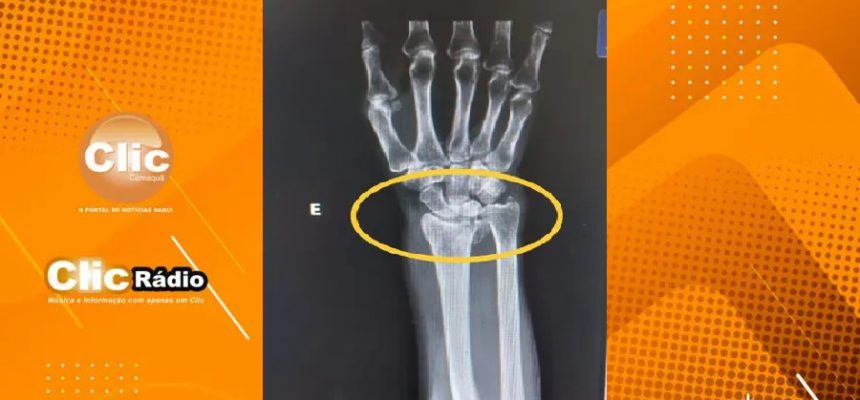

Um homem de 41 anos foi preso preventivamente por quebrar o braço da própria mãe, de 66, na localidade de Santa Marta, no interior de Ibarama, a 245 Km de Porto Alegre. Segundo a delegada Graciela Foresti Chagas, que coordenou as investigações, o suspeito derrubou a vítima no chão e arremessou uma cadeira nela. Ele ainda teria tentado arremessar a mesa da cozinha e também dar golpes de faca na idosa. As informações são do g1 RS.

Por causa da lesão, a idosa vai precisar fazer uma cirurgia de reconstrução, mas ela já está em casa e passa bem.